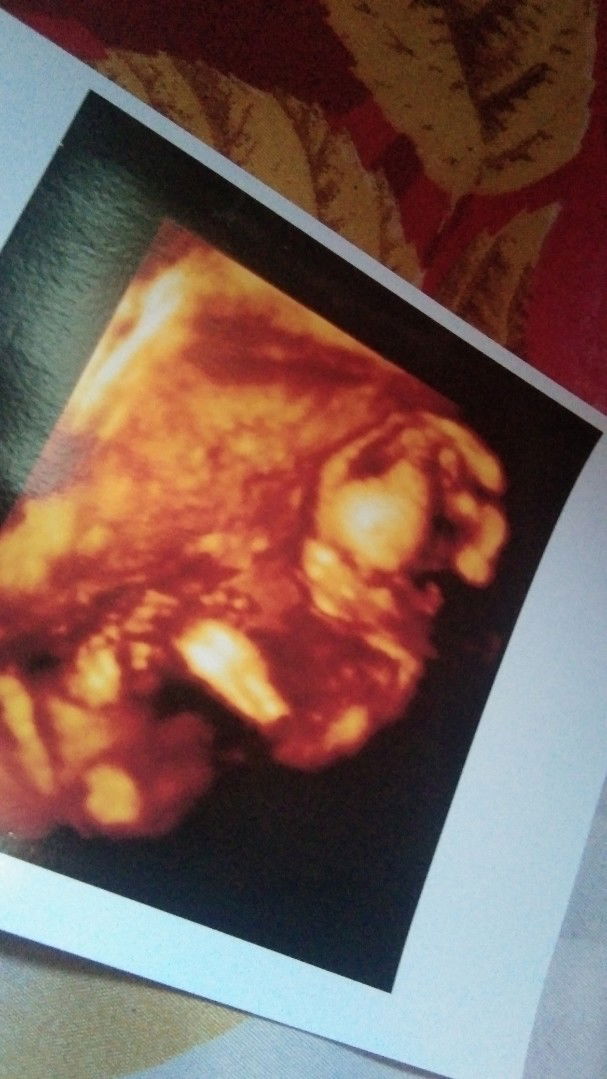

Bolehkah bumil tidur pagi???¿

di beberapa artikel yang saya baca, bumil dianjurkan untuk tidak tidur pagi bund.. karna mempengaruhi perkembangan janin..